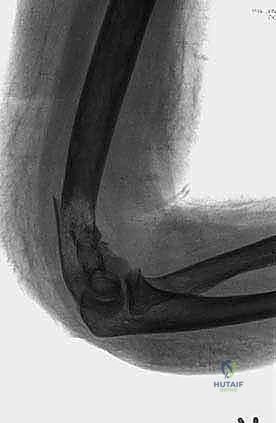

- النوع الثالث (العضد البعيد - Distal Humerus): يمتد إلى لقم العضد أسفل الحواف فوق اللقمية بالقرب من مفصل الكوع. الجراحة هنا معقدة جداً بسبب قرب الشريان العضدي والأعصاب (الزندي، الناصف، والكعبري)، وقد تتطلب دمجاً للمفصل أو استبدال مفصل الكوع.

كذلك، في أورام العضد القريب (قرب الكتف)، يجب حماية العصب الإبطي (Axillary Nerve) والشريان المنعطف. وفي أورام العضد البعيد، يجب حماية العصب الزندي (Ulnar Nerve) الذي يمر خلف الكوع. إن هذه الدقة التشريحية هي ما يميز الخبير عن غيره، وهي ما يضمن للمريض في صنعاء خروجاً آمناً من غرفة العمليات.